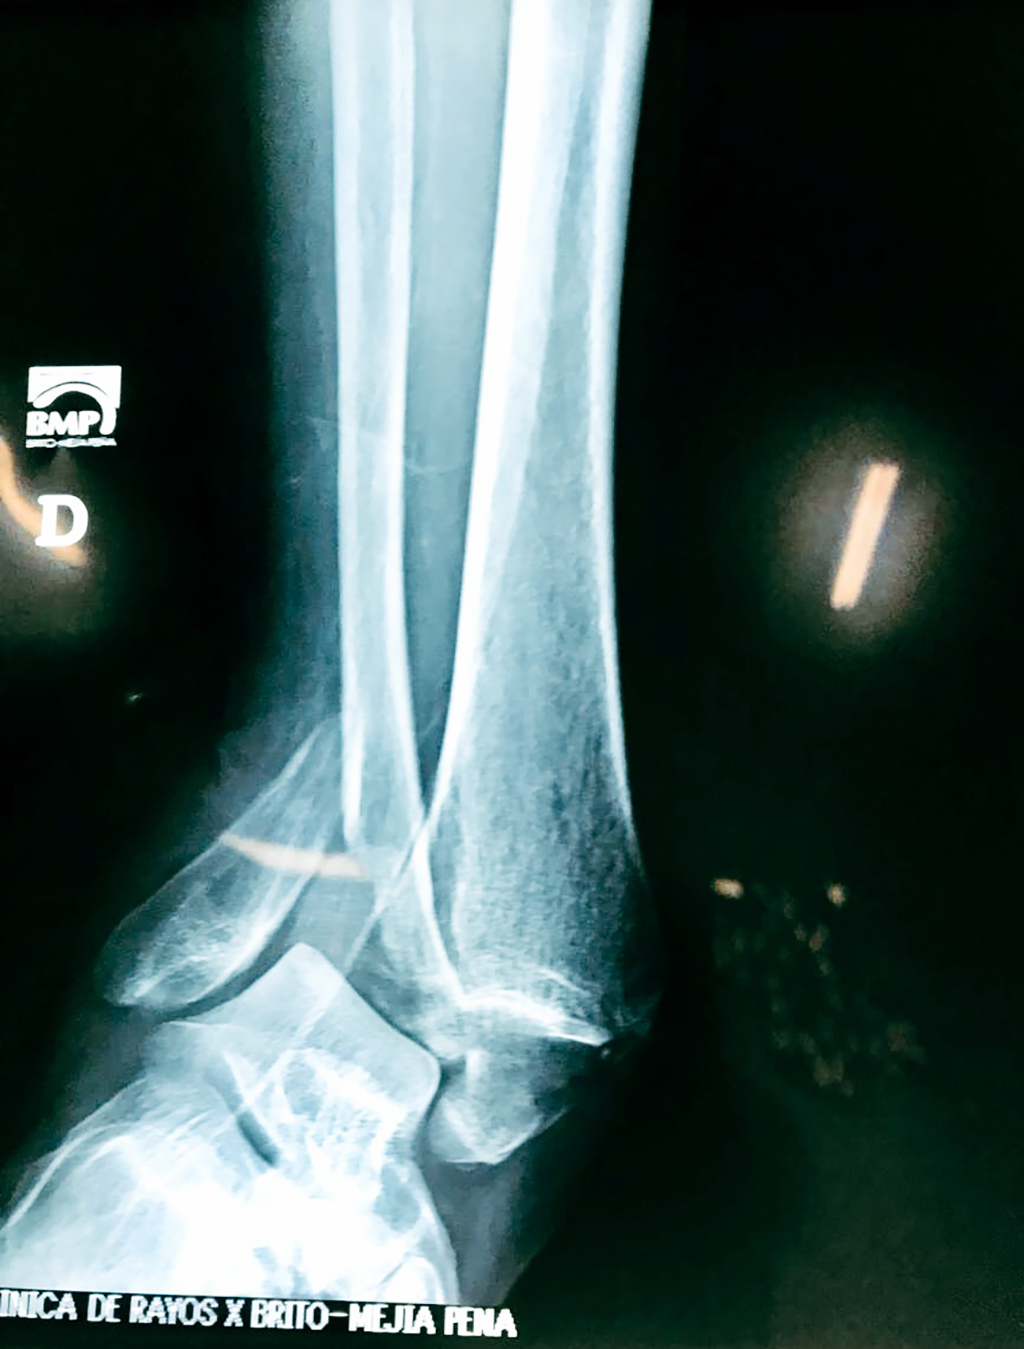

Una fractura de tobillo es la rotura de uno o más de los huesos del tobillo. Estas fracturas pueden ser:

Algunas fracturas de tobillo pueden requerir cirugía si:

- Los extremos de los huesos están desalineados entre sí (desplazados).

- La fractura se extiende hasta la articulación del tobillo (fractura intra-articular).

- Los tendones o ligamentos (tejidos que sujetan los músculos y los huesos entre sí) están rotos.